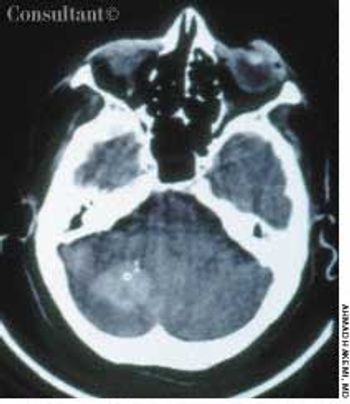

A 57-year-old man complained of a severe headache of sudden onset while he was lifting heavy boxes. Within minutes, he collapsed and became unconscious. On arrival at the emergency department, the patient was deeply comatose. His pupils were 7 mm, fixed, and unreactive to light; brainstem reflexes were absent, and he was unresponsive to noxious stimulation. His blood pressure was 210/120 mm Hg; he had no known history of hypertension.